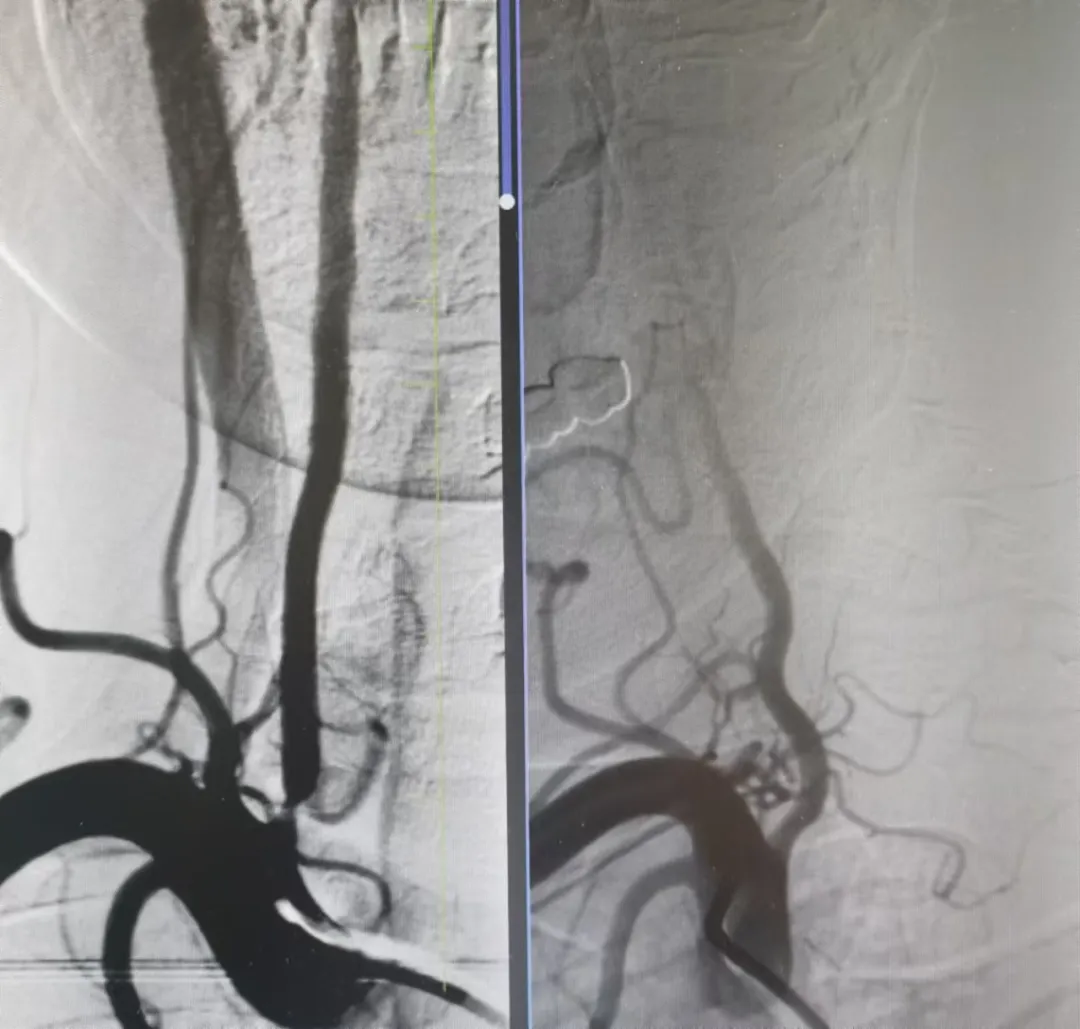

打通腦血管狹窄患者生命線丨國(guó)文醫(yī)院一天完成多例神經(jīng)介入手術(shù)

近日,國(guó)文醫(yī)院神經(jīng)介入科團(tuán)隊(duì)在丁金明主任和朱洪波副主任帶領(lǐng)下成功為兩例腦血管狹窄患者開通幾近閉塞血管得到患者和家屬一致好評(píng)該項(xiàng)技術(shù)自開展以來已為本地區(qū)眾多腦動(dòng)脈狹窄患者帶來福音 閱讀量:2777